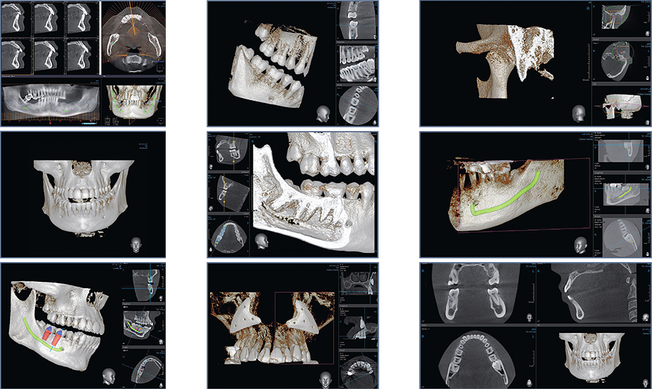

A CBCT (CT Scan) is a special type of digital X-ray that captures multiple images from different angles and combines them into a detailed 3D model of your teeth, jawbone, and surrounding structures. It reveals important anatomy such as nerves and sinuses- all while using low radiation and taking only a few seconds.

This quick, comfortable, and non-invasive scan helps Dr. Kim make precise diagnoses and create the most effective treatment plans, often eliminating the need for exploratory procedures.

3D imaging allows us to locate the lower jaw nerve relative to wisdom teeth, reducing the risk of nerve injury and ensuring safer, more predictable extractions.

For successful implant placement, it’s essential to know the bone height, width, quality, and angulation, as well as the location of nearby anatomy. CBCT provides accurate information for precise and long-lasting results.

We can view unerupted or impacted teeth in 3D, helping plan orthodontic treatments with greater confidence and precision.

By identifying all root canals before starting treatment, CBCT enables Dr. Kim to perform root canal procedures more effectively and with fewer surprises.